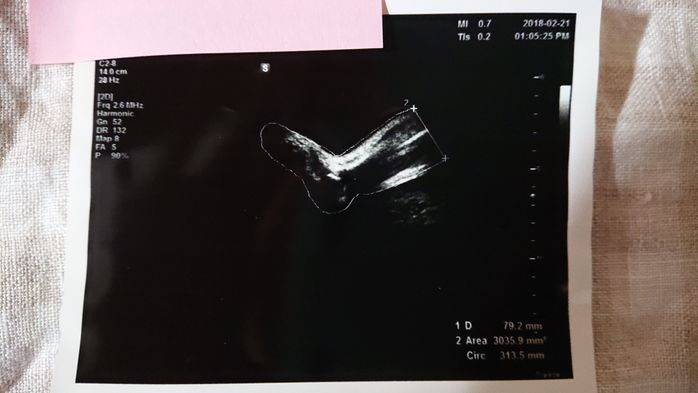

《妊娠36週目のエコー写真》

帝王切開手術の予定日から1週間前、妊娠36週目のエコー写真です。妊婦健診では「逆子が戻っていますように」と毎回願うのですが、この時も戻らず。でも、医師や看護師から「出産直前にも最終チェックするからね。その時に急に戻ってる赤ちゃんだっていたことあるから」と励まされました。切迫早産で24時間点滴が繋がっている状態では逆子体操もできないので、「戻れ~、戻れ~」と、願う事しかできませんでした。エコー写真は赤ちゃんの足です。